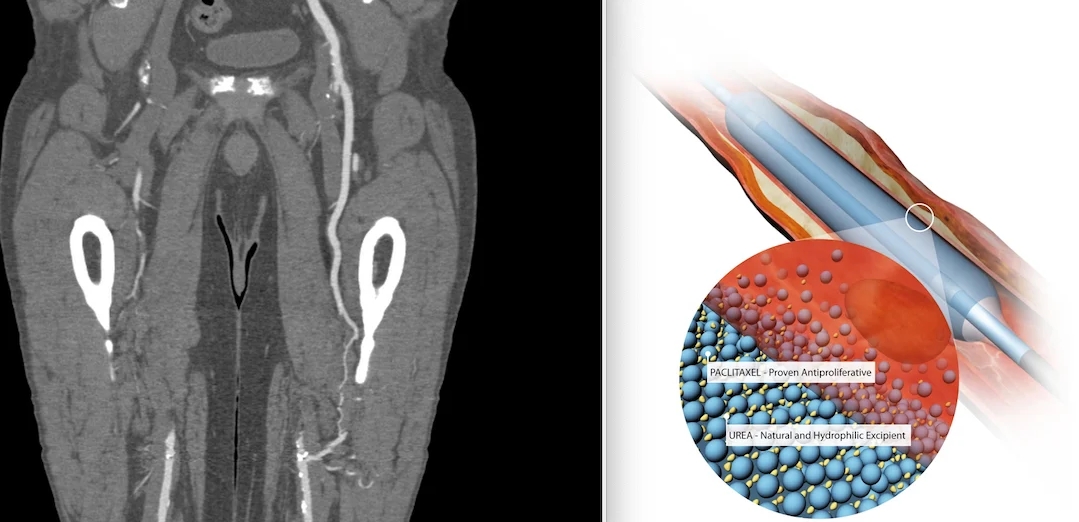

New long-term data from the Safety Assessment of Femoropopliteal Endovascular Treatment With PAclitaxel-coated Devices (SAFE-PAD) study were presented today as